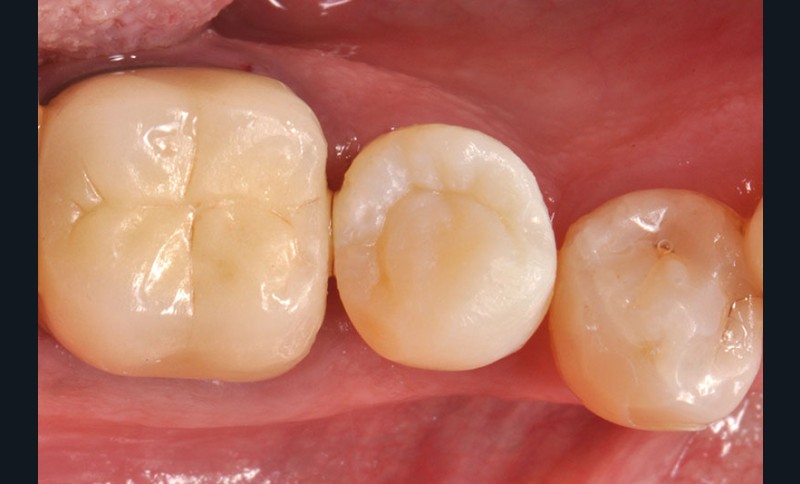

34, 35. Vues vestibulaire et occlusale de la prothèse d’usage collée sur 45 (Laboratoire du Sud-Ouest).